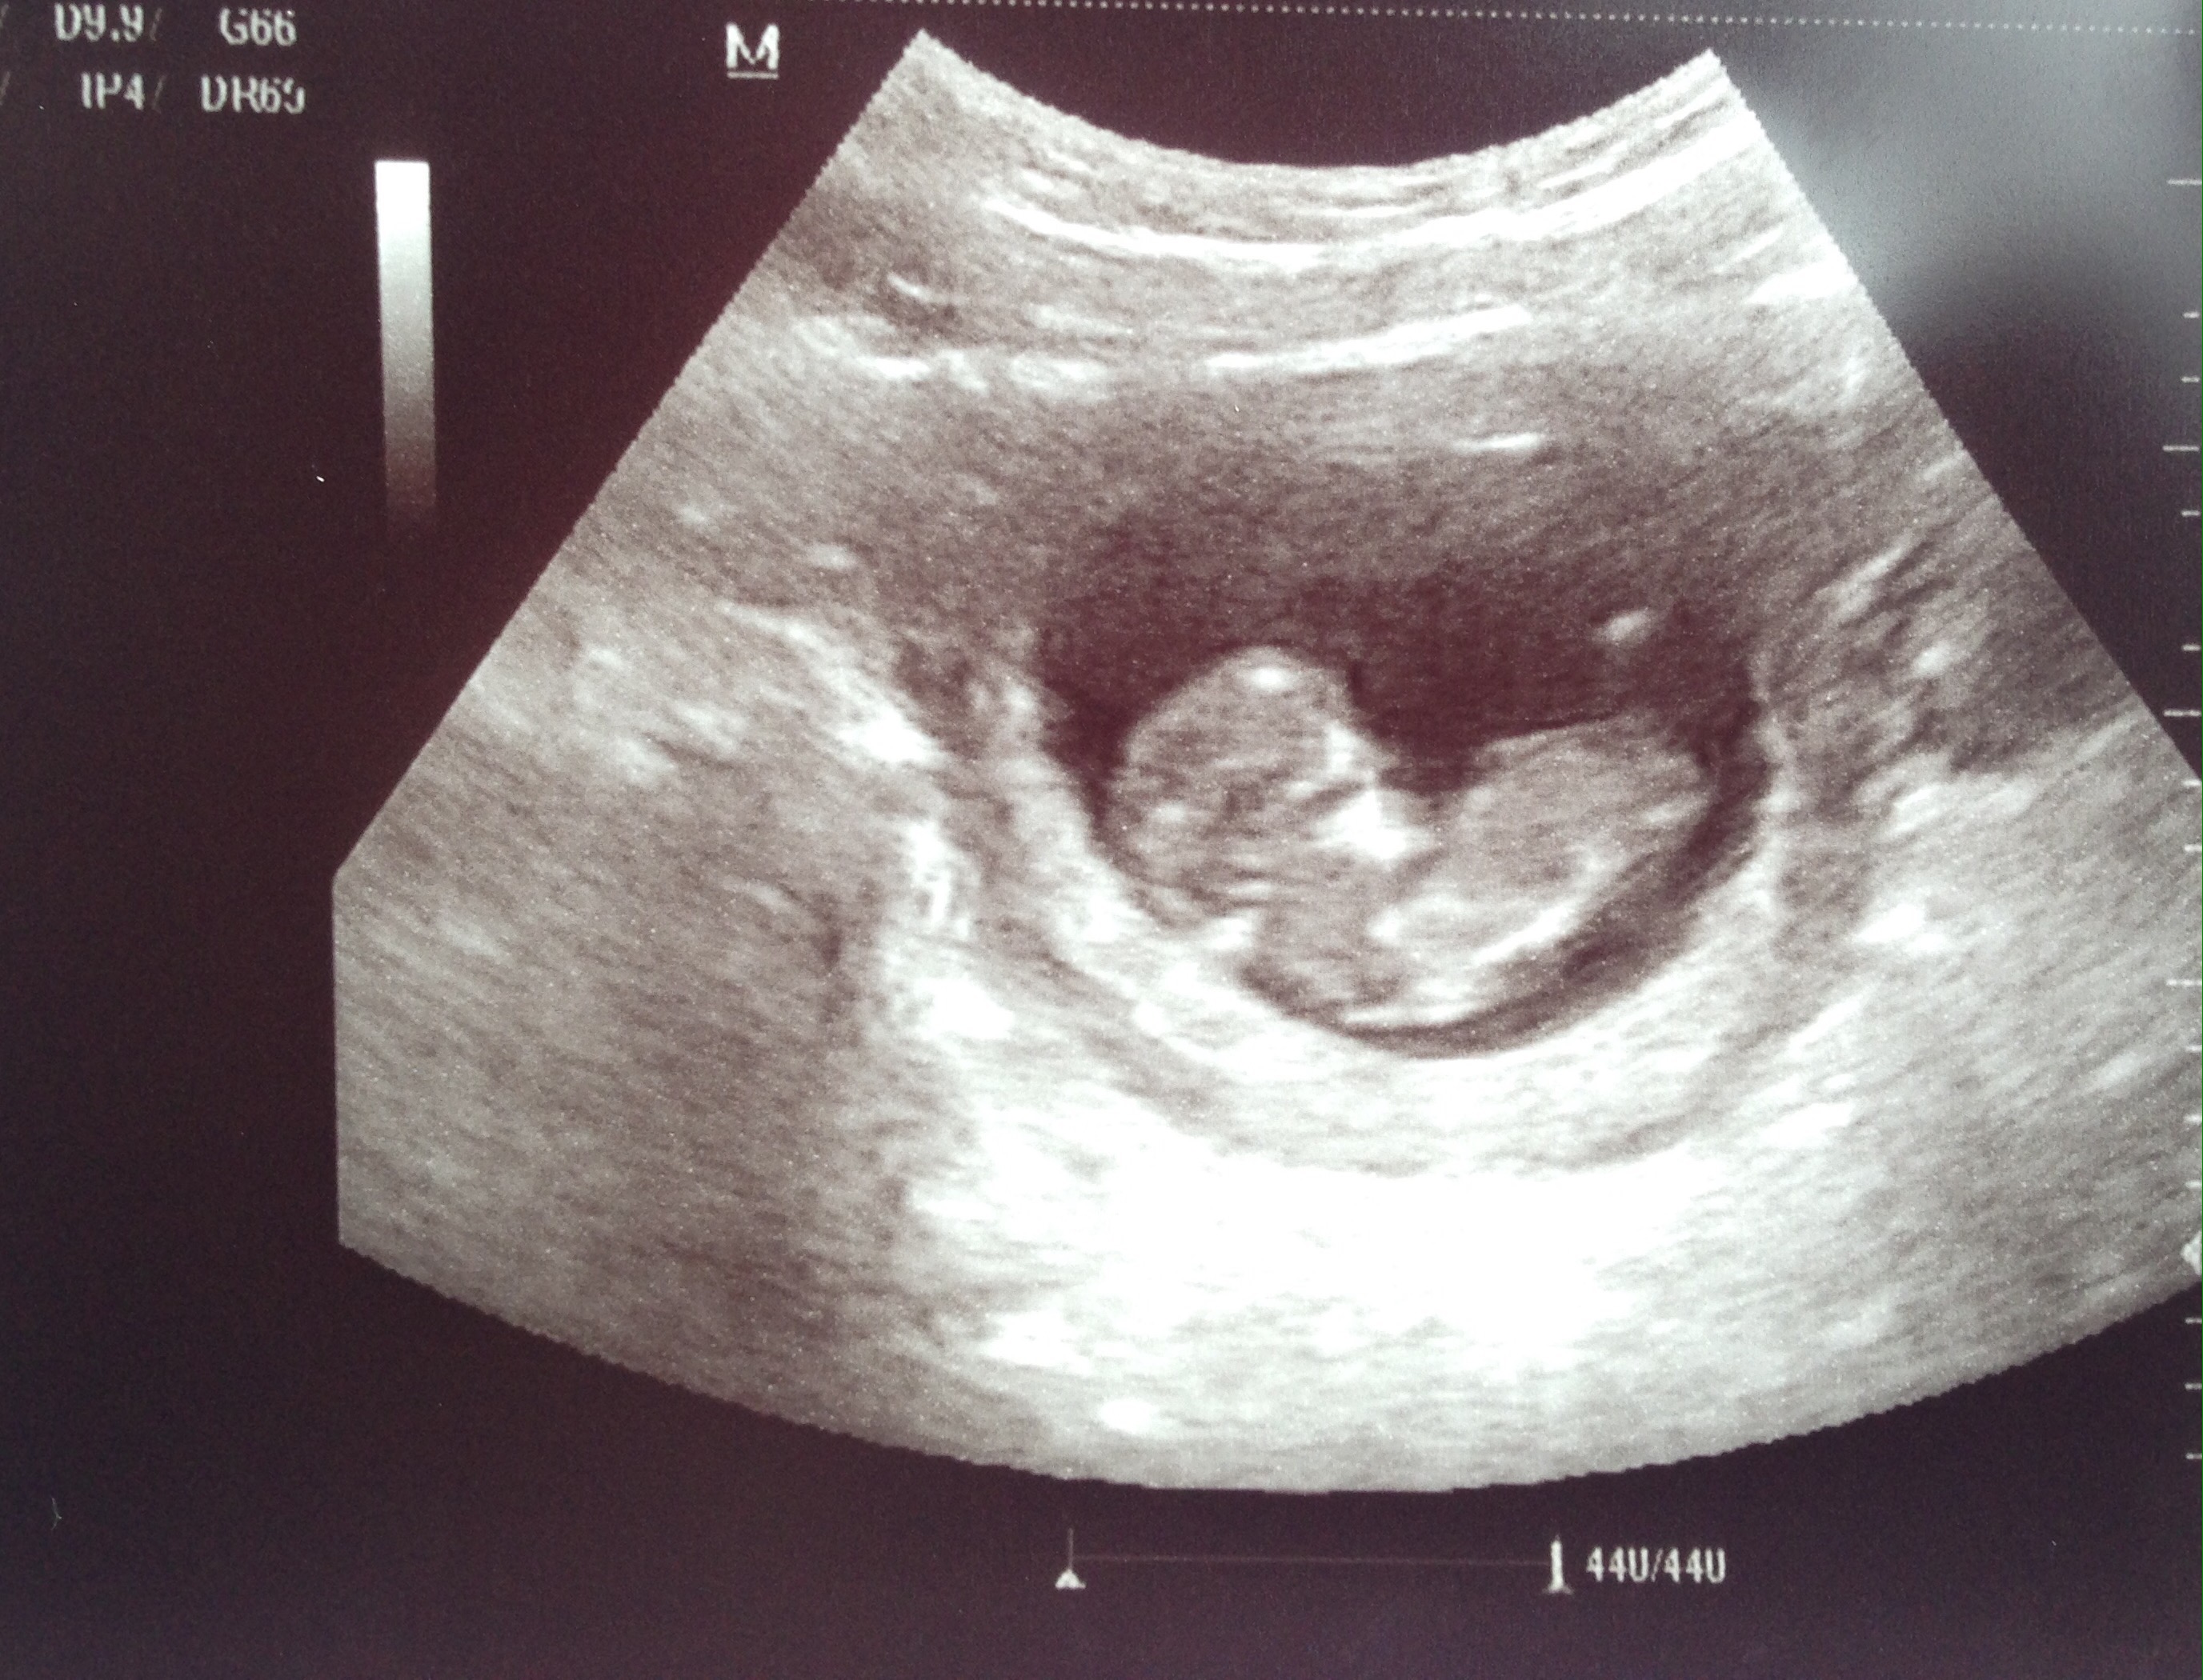

Since I couldn’t post any baby related pictures over the last 13 weeks I’ve posted some below to help catch you up. Over the next few months I’ll try to keep you guys updated on the highs and lows of pregnancy so stay tuned!